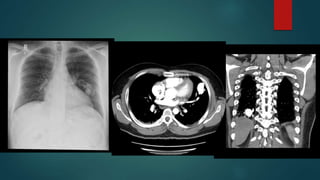

Posterior mediastinal mass